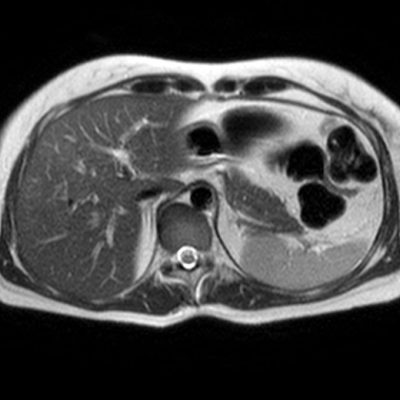

El estudio se complemento con resonancia magnética, donde se demostró la presencia de múltiples imágenes focales hepáticas confluentes con disminución de la señal en secuencias fuera de fase, no mostrando alteración de la señal en secuencias potenciadas en T2, sin signos de restricción al pulso difusión ni refuerzos anómalos luego de la administración de contraste endovenoso, estos hallazgos confirman la sospecha de esteatosis focal multinodular (fig. 5, 6 y 7).